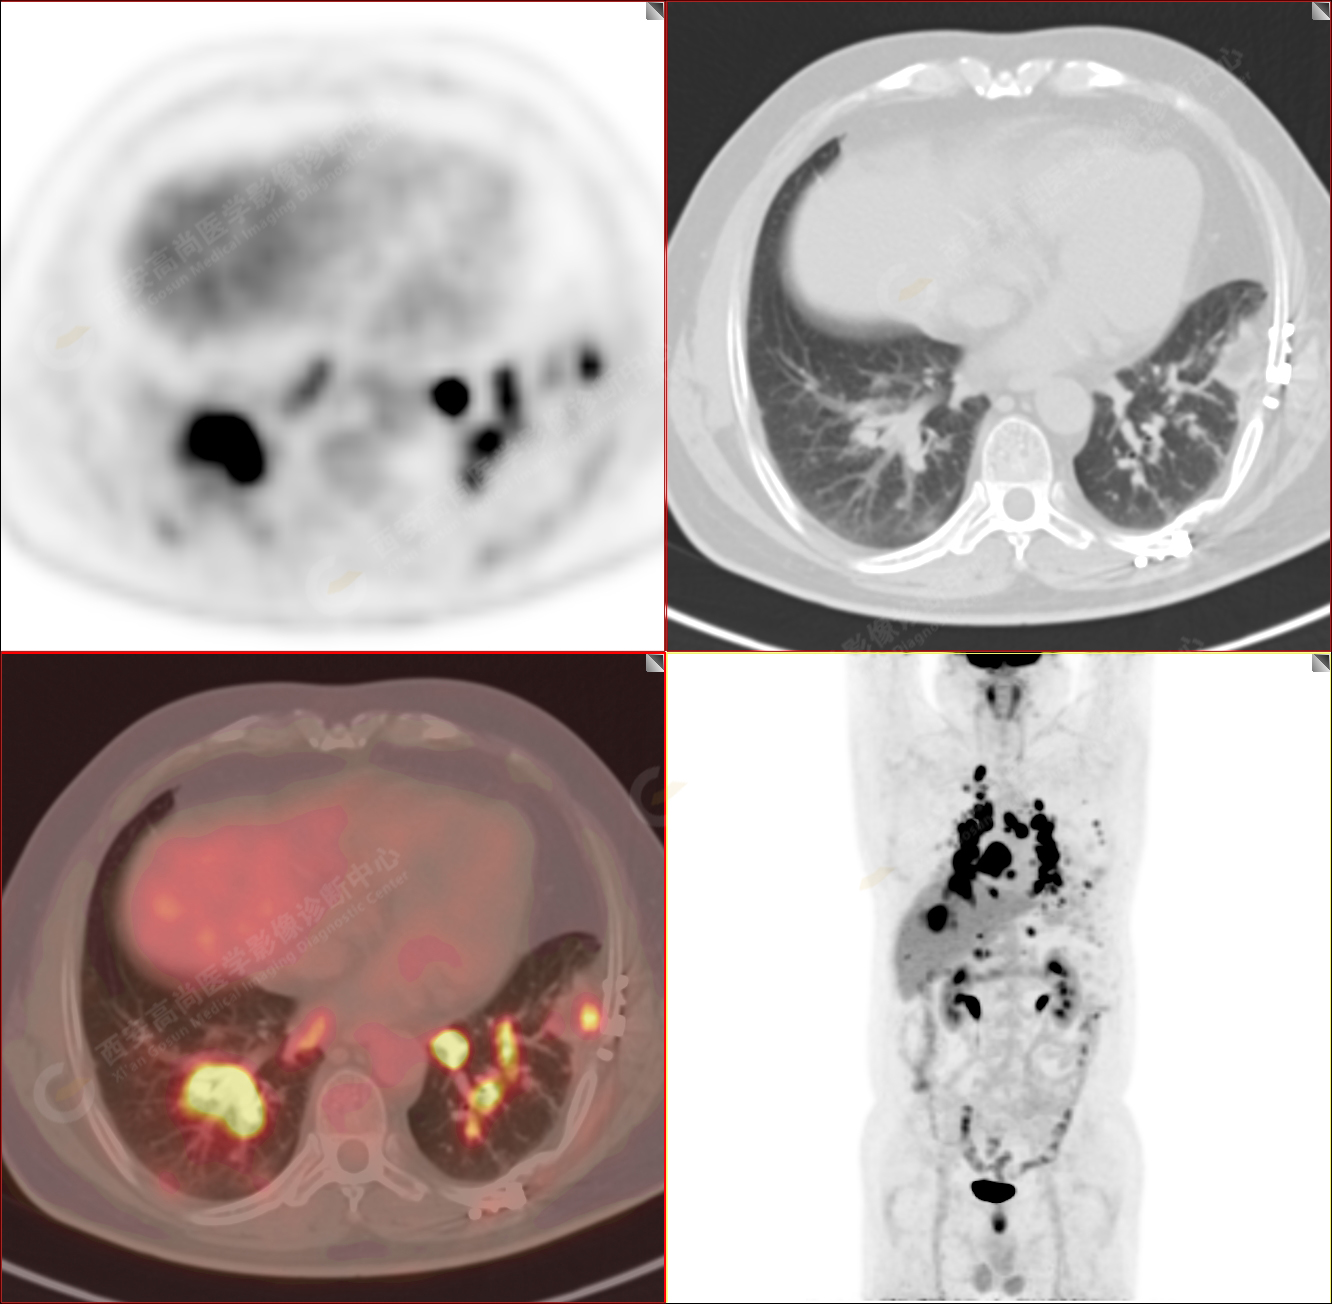

PET/CT-MR診斷結(jié)節(jié)病雙肺及全身多發(fā)淋巴結(jié)廣泛累及1例【西安高尚病例】

男性,53歲,頭暈半月入院,CT發(fā)現(xiàn)肺內(nèi)腫塊,雙肺多發(fā)大小不等實(shí)性及粟粒樣結(jié)節(jié),雙肺門(mén)及縱隔多發(fā)腫大淋巴結(jié)。病程中無(wú)發(fā)熱、胸悶氣及胸部不適。既往:左側(cè)肋骨外傷史。

PET/CT圖像